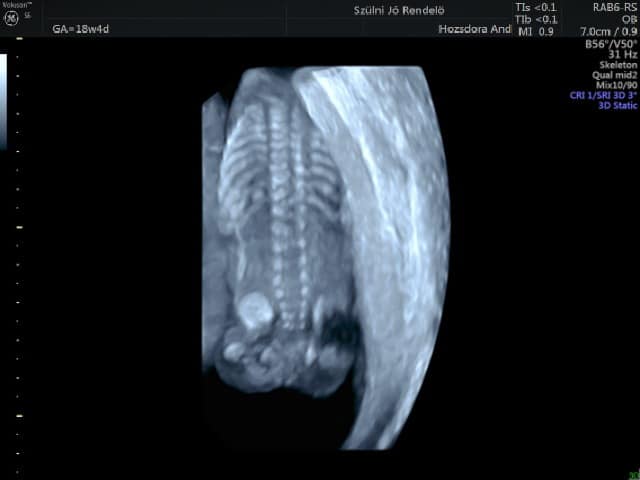

Csontrendszer: A csontosodási folyamatok felgyorsulnak, az apróbb csontok szépen láthatóvá válnak, már jól lehet vizsgálni az ujjakat, ujjperceket, a gerincet, a csigolyák nyúlványait, a csigolyatestet, emiatt ekkor könnyebb (de nem könnyű) megtalálni a gerinc rendellenességeit is. Azonban a gerinc rendellenességek bizonyos formái könnyebben rejtve maradhatnak, ha például bőrrel fedettek, vagy nehéz a területhez hozzáférni, nehezen vizsgálható magzatoknál. Emiatt nagyon fontos a jó pozíció kivárása vizsgálat alatt, vagy kontroll vizsgálatra visszahívni a kismamát. A lábak és a kezek vizsgálata is könnyebben kivitelezhető, mint később, mert a magzat körül még arányaiban több tér van, és mozgékonyabbak is a kis magzatok.

A 3D ultrahang kiegészítő vizsgálat, nem helyettesíti a 2D ultrahangot. Magzati ultrahangnál jól használható a koponya, gerinc és a csontrendszer kiegészítő vizsgálatára, valamint különböző eltérések megjelenítésére is. Emiatt a II. trimeszteri vizsgálatnál a legtöbb szűrőcentrumban használjuk.